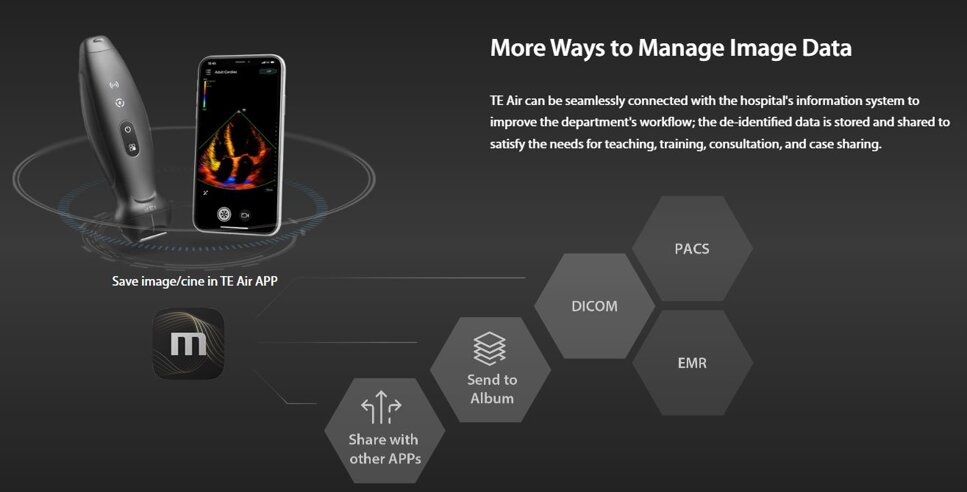

TE Air può essere collegato senza soluzione di continuità al sistema informativo dell'ospedale per migliorare il flusso di lavoro del reparto; i dati anonimizzati vengono archiviati e condivisi per soddisfare le esigenze di insegnamento, formazione, consulenza e condivisione dei casi.